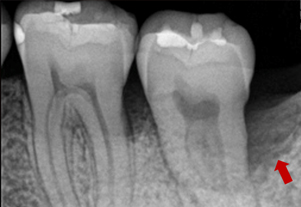

症例3(再生療法)

Before

After

- POINT

- 他院で歯周病の治療をしていましたが、なかなか歯周病が改善されず、セカンドオピニオンにて来院された患者様です。歯周病の進行した部分に再生療法を行い(エムドゲインを使った歯茎の手術)ホームケアを徹底することで改善されました。

今後も継続したメインテナンスが必要です。